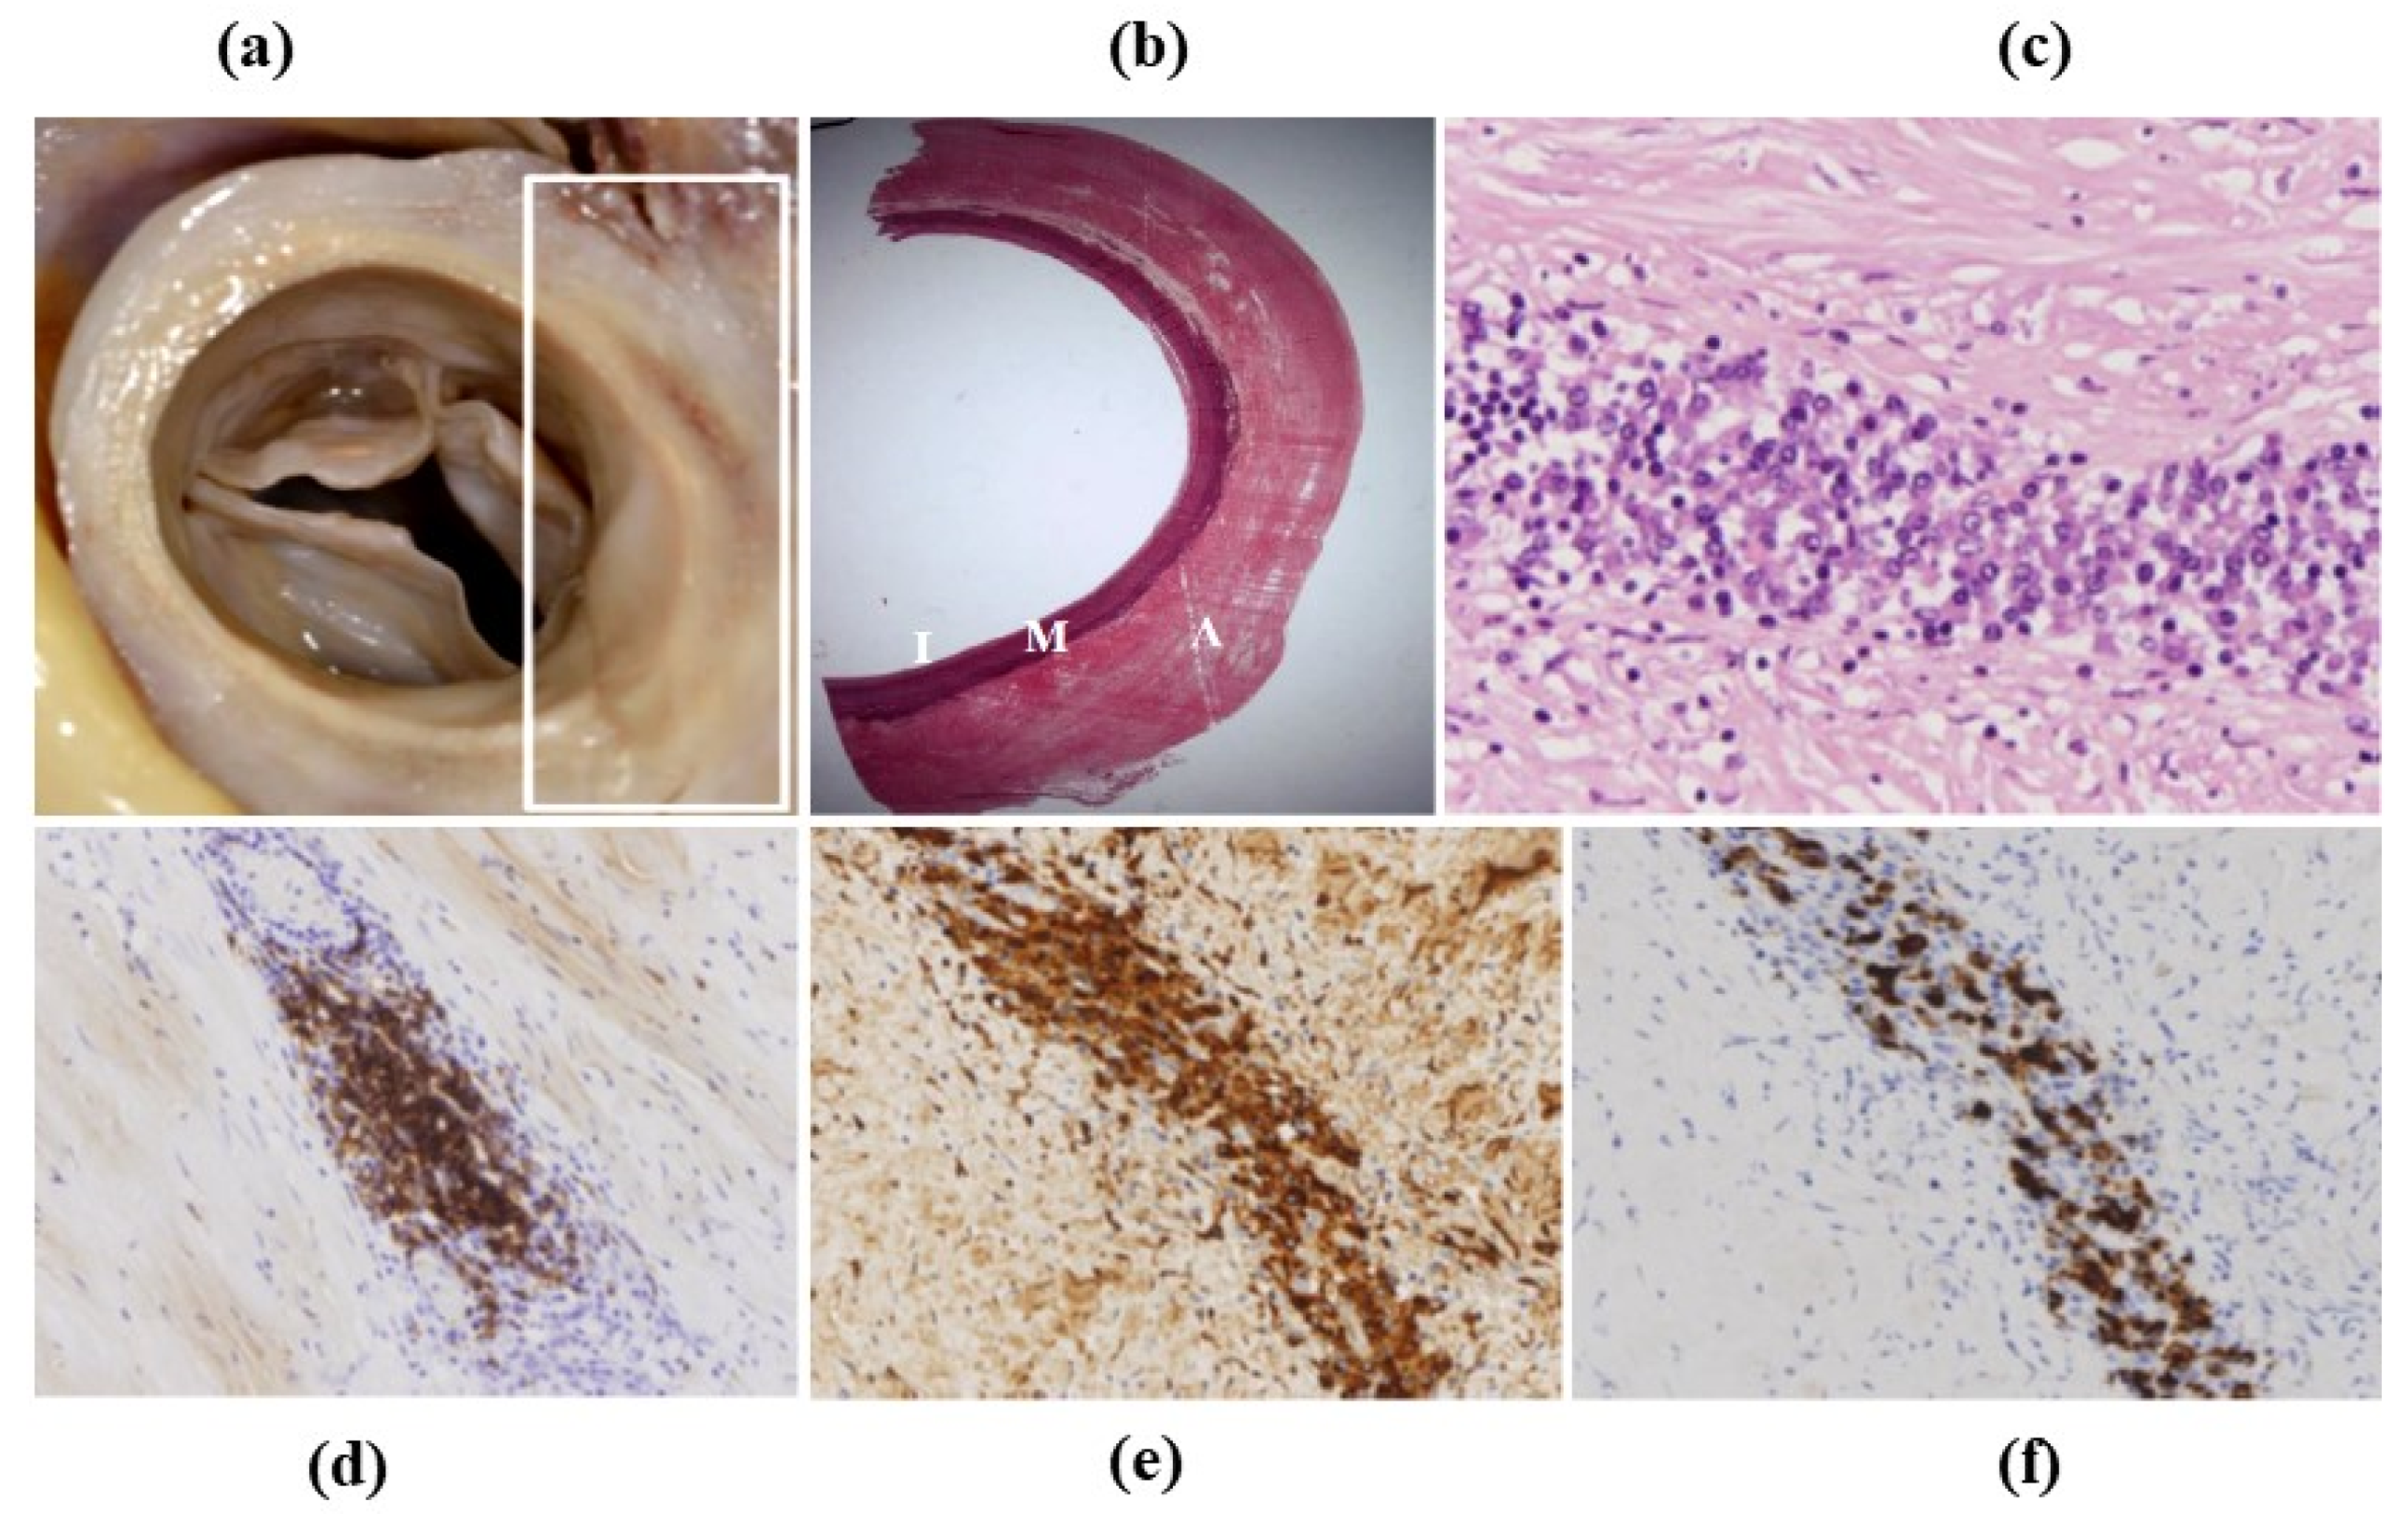

- Decellularization in unimplanted allografts appeared complete, both in the lamellar units of the tunica media and valvular interstitium with disappearance of endothelial lining (Figure 31);

- Cellular repopulation was observed in the outer part of implanted homograft wall by novel smooth muscle cells in the lamellar units (Figure 32a,b) and in the intima with a novel myointimal layer; this layer was noticed also in small animals such as rodents [68]. Novel endothelial cells appeared to line both the aortic wall intima and inflow/outflow at the cusp surface, as well as vasa vasorum, and valve spongiosa appeared repopulated by interstitial cells (Figure 32c,d);

- The undifferentiated nature of the repopulated cells is demonstrated by colocalization of some biomarkers. Novel wall cells showed positivity both for α-SMA and vimentin and novel cusp cells for SMA, vWF, VEGF, VEGF R2, α-SMA and CD57 (HNK-1), which is a neural crest marker;

- Cell density, when compared to non-decellularized control allografts, showed 20% repopulation both in the aortic wall and at the cusp level (Figure 34);